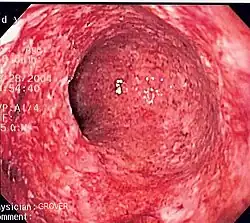

Endoscopic image of colon cancer identified in the sigmoid colon on screening colonoscopy for Crohn's disease

Some studies suggest there is a role for chemoprotection in the prevention of colorectal cancer in Crohn's involving the colon; two agents have been suggested, folate and mesalamine preparations.[59] Also, immunomodulators and biologic agents used to treat this disease may promote developing extra-intestinal cancers.[60]